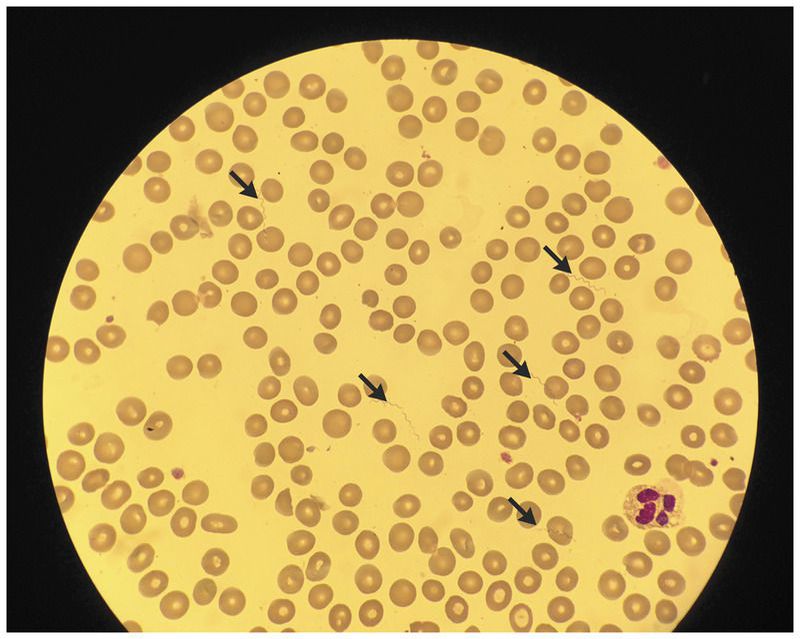

After collapsing in Munich, Germany, a 16-year-old male Somalian refugee was brought to a local hospital with severe headache and abdominal pain. His vital signs were notable for a temperature of 41°C, a heart rate of 105 beats per minute, blood pressure of 95/50 mm Hg, and an oxygen saturation of 98% while he was breathing ambient air. On examination, he appeared to have decreased consciousness and abdominal tenderness. Laboratory findings were notable for leukocytosis (>17×109 white cells per liter), an elevated C-reactive protein level of 250 mg per liter, a procalcitonin level of 17.6 ng per milliliter, and thrombocytopenia (47×109 platelets per liter). No malaria parasites were seen on the blood smear, but spirochetes were visible (arrows), a finding that suggested louseborne relapsing fever. The diagnosis was confirmed by means of a polymerase-chain-reaction assay. The patient was treated with doxycycline. Fever and mild hypotension developed shortly after the initiation of treatment, consistent with a Jarisch–Herxheimer reaction, and subsided when intravenous fluids were administered. The patient had a full recovery. Borrelia recurrentis is transmitted by body lice. Humans are the only host. After an incubation period of approximately 7 days, the illness is characterized by recurring episodes of high fever, headache, muscle and joint pain, nausea, and vomiting, with each episode lasting several days. Clinicians caring for refugees should be aware of the epidemiologic features and clinical picture of this disease. When this condition is left untreated, mortality can be up to 70%.